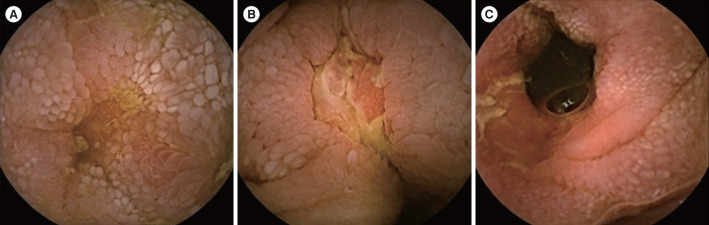

Results: Among 3,752 patients, 24 (0.6%) were diagnosed with Crohn's disease using video capsule endoscopy findings. The disease location (P< 0.001) and behavior at diagnosis (P= 0.013) of the cases significantly differed from that of controls. The perianal fistula modifier (25.0% vs. 33.3%, P= 0.446) did not differ significantly between the 2 groups. Initial disease activity and C-reactive protein and fecal calprotectin levels were significantly lower in cases versus controls. The median Lewis score was 838 (interquartile range, 393-1,803). Over 10 years of follow-up, the cases showed significantly lower cumulative risk of complicated behavior, biologics use, Crohn's disease-related hospitalization, and surgeries (log-rank test P< 0.05).